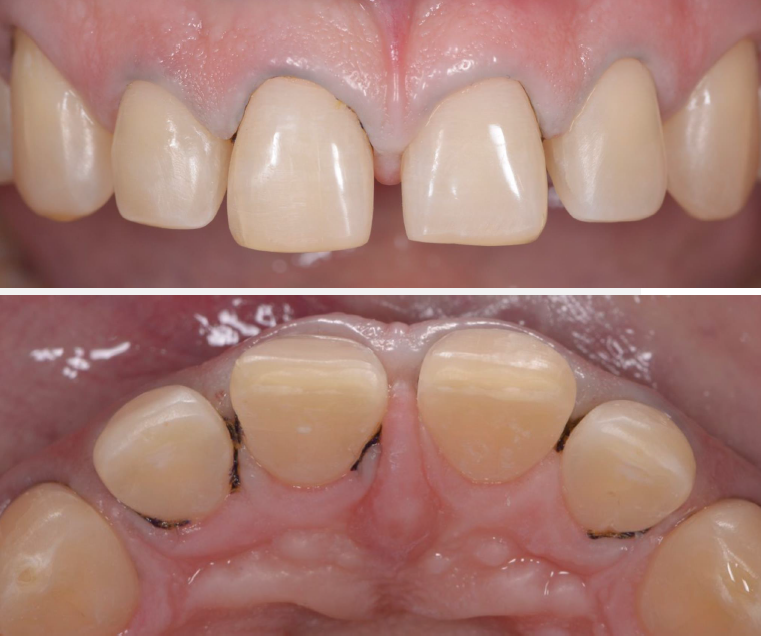

Close-up of teeth with the mouth slighty open

3M™ Protemp™ 4 Temporization Material mock-up placed with a wax-up impression.

A close-up of teeth sowing the upper jaw and a ping material

Preparation guide fabricated on the final wax-up was used to control the space needed for ceramic veneers: view before and after the minimal preparation of incisal and interpoximal areas.